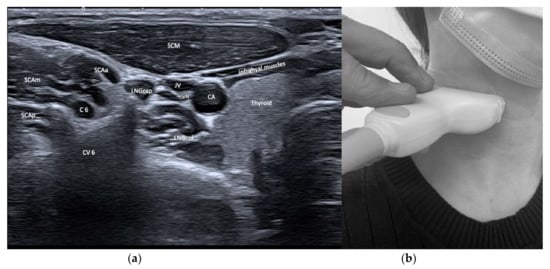

| Longus capitis (LNGcap) | Anteflexion of head and neck | +++ | +++ | Carotid artery, jugular vein, vagus nerve, phrenic nerve | Authors recommend a transoral injection |

| Longus colli (LNGco) | Anteflexion of neck | +++ | +++ | Carotid artery, jugular vein, vagus nerve, phrenic nerve | Authors recommend a transoral injection |

| Scalenus anterior (SCAa) | Anteflexion of neck | +++ | +++ | Thyroid, carotid artery, brachial plexus, phrenic nerve, lung | |

3.4. Safety Issues and Imaging of Relevant Neighboring Structures